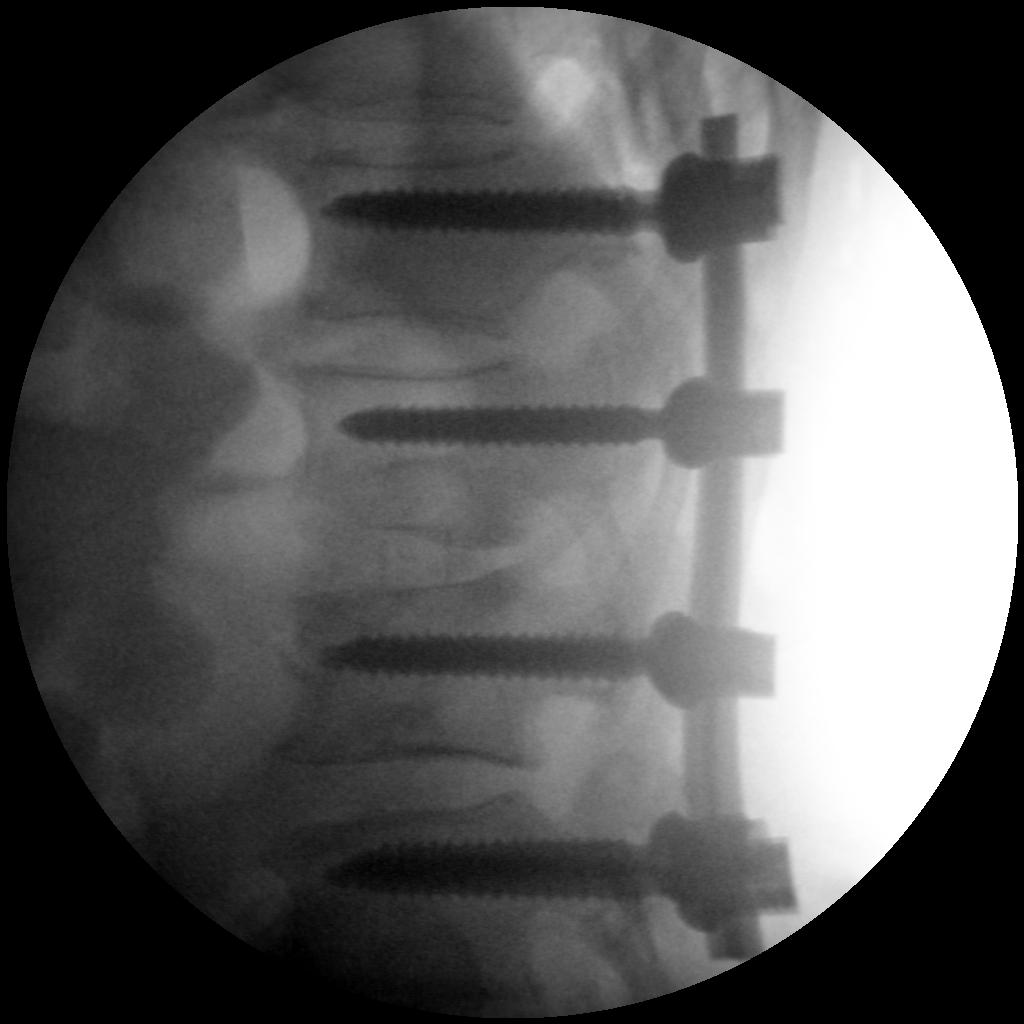

Hip Diagnostic and therapeutic spinal

Skan-C uses advanced imaging technology, such as pulsed fluoroscopy and digital subtraction angiography, to provide highly detailed images of the affected area. This allows doctors to perform procedures with increased precision and accuracy, and better patient outcome

Intelligent algorithms continuously monitor the image quality and adjust parameters to provide best image quality at lowest possible radiation. Ultra-high frequency generator (80-250 kHz), low dose mode, pulse mode, laser aimer, virtual collimator, etc. are features that lowers radiation for the safety of your patients and staff